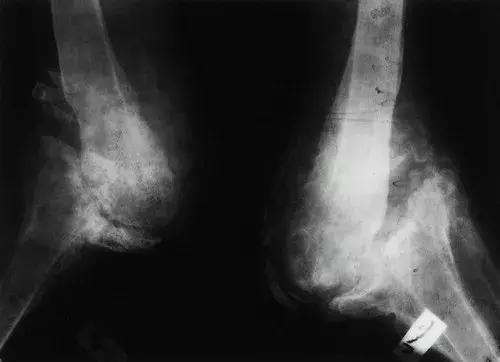

图9:68岁男性,患有长期神经梅毒,膝关节的神经性骨关节病。X线片显示 股骨远端变形,形状像鸡腿。 胫骨横向半脱位,伴有外翻角。 存在明显的关节周围骨质碎屑。 在梅毒患者中,骨关节病最常影响膝关节。